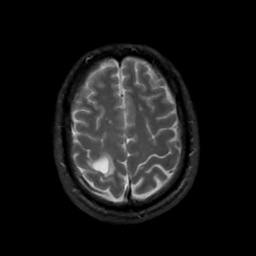

MR Study #6, March 17, 1991 -- Slice #40

[Home][Help][Clinical][Tour 1][Tour 2] Slice 40